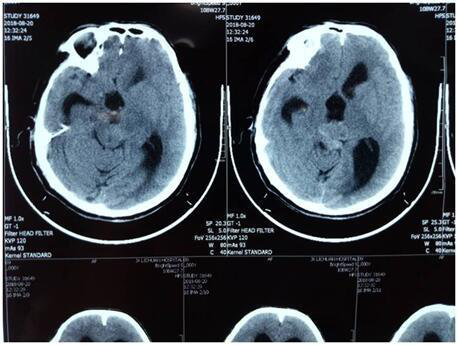

家住鄞州区的57岁陈老伯半年前突然出现莫名其妙的头疼,每次发作,疼痛都从他的头脑中向外辐射,严重时脑袋有“爆裂”的感觉。尤其近两个月不仅头疼的症状加重,还出现了走路不稳的情况,甚至连闭眼站立都天旋地转。家人赶紧将其送到鄞州人民医院神经外科就诊,经核磁共振检查发现,陈老伯颅内松果体区有一核桃般大小的肿瘤。

“因肿瘤位于大脑中央位置,累及脑内多根大血管,并且靠近脑干,伴有脑积水,手术难度及风险均很大。但如果不进行手术摘除,任由肿瘤继续长大则会严重影响陈老伯的生活,甚至威胁到生命……”。接诊的该院神经外科高峰博士考虑再三,在征得患者及家属的同意下,最后决定为他制定出详细的围手术期治疗和肿瘤切除方案。

手术当日,高峰主任在显微镜和神经内镜内镜配合下为其行“微创开颅松果体肿瘤切除及侧脑室钻孔引流术”,术中发现肿瘤呈淡红色,鱼肉状,约2cmx2cmx2cm大小,被两侧的脑深部大静脉包绕,并从后向前挤压脑干,肿瘤供血极其丰富,操作空间极其狭小,每切一块肿瘤都冒着很大的风险,稍有损伤便会导致严重出血、水肿、昏迷等后果。整个手术在精雕细刻下持续了近5个小时,凭借精湛的医术,高峰主任最终为陈老伯成功切除了全部肿瘤。术后患者没有出现任何并发症,现已出院回家休养中。